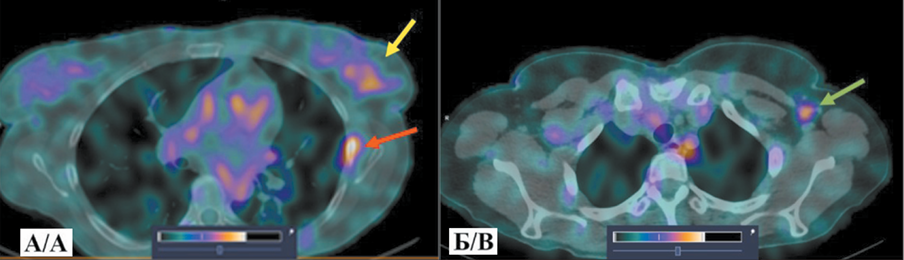

Клинический случай № 2. Пациентка Д., 42 года, диагноз: Рак правой молочной железы IV стадии (T1N1M1), метастаз в аксиллярный лимфоузел, множественные метастазы в костях. ОФЭКТ/КТ проведена через 2 ч после инъекции РФЛП [99mTc]Tc-DB8 в дозировке 80 мкг, при которой помимо визуализации первичного очага и метастатически измененного лимфоузла выявлена высокая аккумуляция РФЛП в проекции LII-SII, в подвздошной и седалищной костях, в заднем отрезке VII ребра справа.

3. Рис. 3. ОФЭКТ/КТ органов грудной клетки больной Д. через 2 ч после инъекции [99mTc]Tc-DB8 в дозировке протеина 80 мкг: А – желтая стрелка указывает на первичную опухоль; Б – зеленая стрелка указывает на метастатический аксиллярный лимфоузел. Примечание: рисунок выполнен авторами